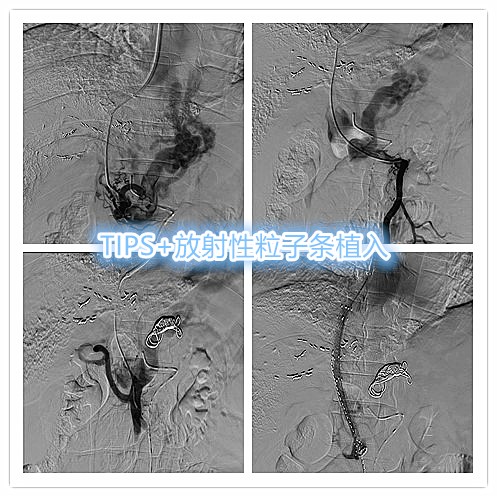

近期出现食管胃静脉曲张破裂出血,予以行TIPS分流减低门静脉压力,联合放射性条植入至门静脉内行癌栓近距离照射治疗,到达标本兼治。

TIPS术+放射性粒子条植入治疗

术后患者腹水减退,腹胀症状明显缓解,显著减低再次消化道出血风险。也为患者后续治疗争取空间。